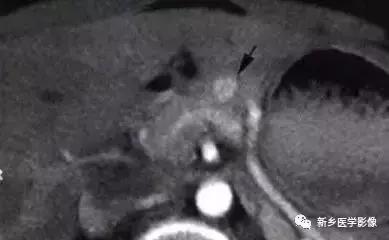

一、胰腺内分泌肿瘤

胰腺神经内分泌肿瘤属少见病变,发病率较低,每年约在百万分之一以下, 在我国最常见者为胰岛素瘤, 约占80 %~ 85 %,其次为无功能胰岛细胞瘤, 占15 %, 胃泌素瘤3 %, VIP 瘤和胰高血糖素瘤分别约占0 .5 %。